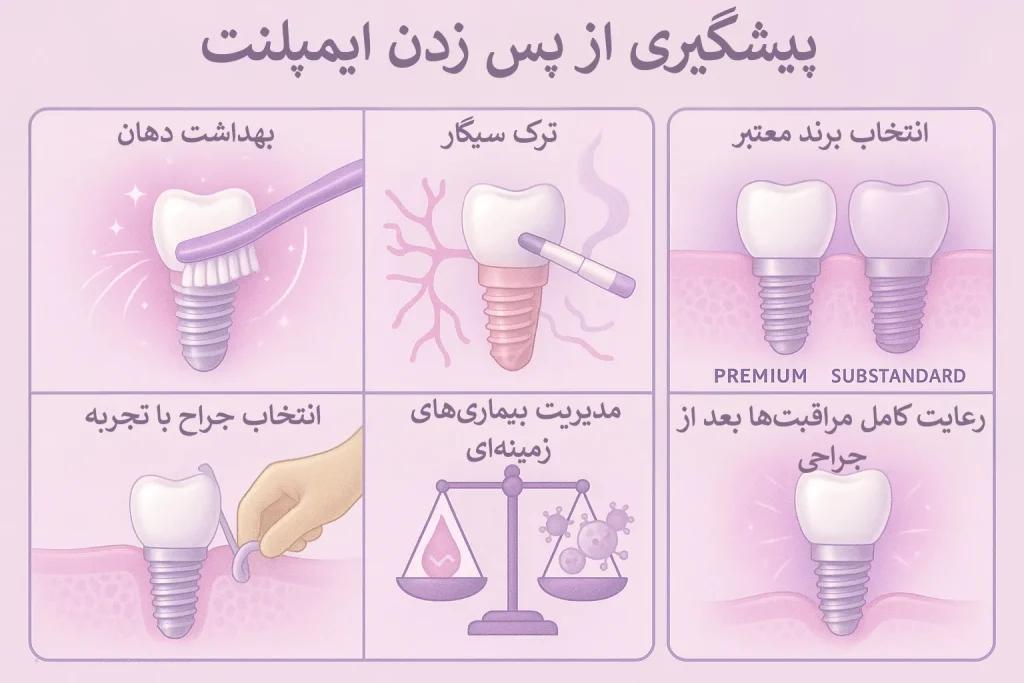

پیشگیری از پس زدن ایمپلنت (نکاتی که ۹۰٪ بیماران رعایت نمیکنند!)

شاید عجیب باشد اما پیشگیری از پس زدن ایمپلنت به اندازه قابل توجهای به خود فرد بستگی دارد. رعایت نکردن نکات بهداشتی، از مهمترین دلایلی است که پس خوردن ایمپلنت را به همراه دارد. بنابراین بهتر است با نکاتی که میتوان برای پیشگیری از پس زدن ایمپلنت رعایت کرد، آشنا شویم.

۱. نگه داشتن بهداشت دهان در اوج

بهتر است روزی دو بار مسواک زدن با مسواکی که فرچه نرم دارد را به عادت تبدیل کنیم. پاکیزه نگه داشتن فضای دهان و دندانها میتواند تاثیر بسیار زیادی در سلامت ایمپلنت دندان داشته باشد.

از طرفی دیگر، برای پاکیزه نگه داشتن فاصله بین دندانها، باید از نخ دندان یا واترجت استفاده کنیم. از آنجایی که فرچه مسواک به فاصله بین دندانها و لثه و ایمپلنت دسترسی ندارد، پس نخ دندان کشیدن از نیازهای ضروری برای حفاظت از دندانها برای جلوگیری از تجمع باکتری و عفونت به حساب میآید. با رعایت تمام نکات بهداشتی، باز لازم است که برای جرمگیری، به صورت دورهای، به دندانپزشک مراجعه کنید.

۲. ترک سیگار قبل و بعد از ایمپلنت

به خوبی میدانیم که سیگار با تنگ کردن رگهای بدن، سرعت جریان خون را کاهش میدهد. بنابراین ترک سیگار میتواند شانس موفقیت ایمپلنت را دو برابر کند.

۳. انتخاب برند معتبر ایمپلنت

هرچه برند ایمپلنت معتبرتر باشد، پس از سطح باکیفیتتری برخوردار است. در نتیجه، جوش خوردن ایمپلنت و ادغام آن با ایمپلنت، سریعتر و بهتر انجام میشود.

۴. انتخاب جراح با تجربه

تخصص جراح از مهمترین نکاتی است که قبل از کاشت ایمپلنت باید در نظر گرفت. هر چه جراح از مهارت بیشتری برخوردار باشد، کاشت ایمپلنت با دقت بیشتری انجام میشود و امکان پس زدن ایمپلنت کمتر میشود.

۵. مدیریت بیماریهای زمینهای مثل دیابت

در صورتی که بیماریهای زمینهای مثل دیابت دارید، قبل از انجام ایمپلنت به دندانپزشک متخصص خود اطلاع دهید. دندانپزشک با در نظر گرفتن شرایط بالینی بیمار، بهترین روش را برای کاشت ایمپلنت انتخاب میکند.

۶. رعایت کامل مراقبتها بعد از جراحی

گرچه دوران نقاهت هر نوع جراحی، دشوار است اما با رعایت چند نکته بعد از جراحی و کاشت ایمپلنت، میتوان خطر پس زدن ایمپلنت را تا اندازه قابل توجهای کاهش داد. این نکات شامل موارد زیر میشود.

- در ۲۴ ساعت اول بعد از جراحی از کمپرس سرد استفاده کنید.

- برای ۲ هفته به خود زمان بدهید و از خوردن غذاهای سفت، پرهیز کنید.

- از دهانشویه طبق دستور پزشک استفاده کنید.